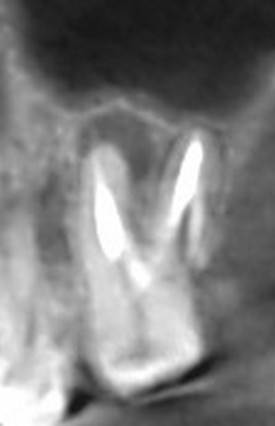

Александр В.В. Опубликовано 29 марта, 2023 Поделиться Опубликовано 29 марта, 2023 (изменено) Здравствуйте! Уже давно на шестом верхнем зубе есть гранулёма или киста размером 5-6 мм. Несколько лет назад пробовали класть кальций в каком-то виде, но, видимо, не помогло. Сейчас всё-таки решил перелечить этот канал, но эндодонтист сказал, что это только часть дела и надо делать все каналы. Кроме того, как я понял, проблема не в том канале, который запломбирован, а в том, который проходит рядом с ним и не был обнаружен и запломбирован. На этом снимке это верхний левый корень и в его правой части темное пятно - это вроде и есть тот ненайденный канал. Здесь видна гранулёма и запломбированный канал (корень слева). А здесь справа от запломбированного канала (левого корня), тот самый незапломбированный. Но у меня есть сомнения по поводу такого вывода, потому что в других каналах можно обнаружить более очевидные "темные каналы" в зависимости от среза. На этих снимках обращаю ваше внимание на правый канал. Если нужно, могу предоставить другие проекции, потому что имею диск с данными КЛКТ. Вопросы. 1. Действительно ли на снимке ненайденный канал на корне зуба с гранулёмой? 2. Возможно ли перелечивание одного канала с гранулёмой или кистой или нужно распломбировать сразу все каналы во всех корнях? 3. Если на снимке всё-таки ненайденный канал, то не кажется ли вам, что он прямой, а не изогнутый? Если прямой, его может обработать терапевт без использования микроскопа? Изменено 29 марта, 2023 пользователем Александр В.В. Ссылка на комментарий